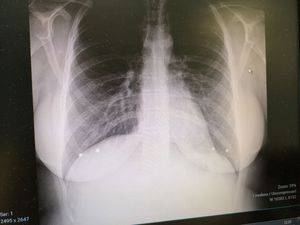

Female patient with nipple piercing RTG